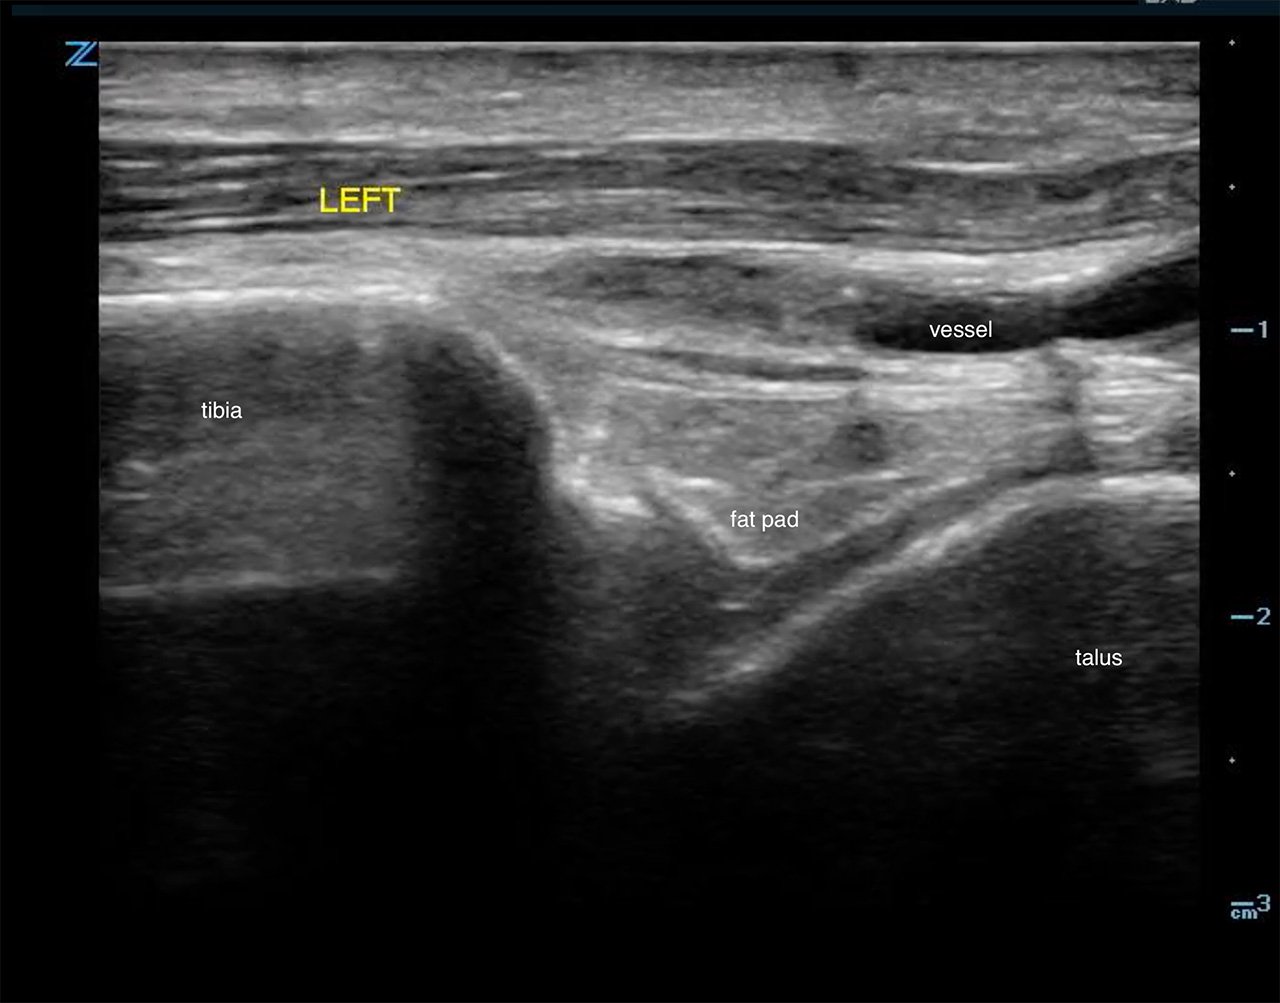

- Identify the hyperechoic tibial cortex and scan distally to the joint space and identify the next shadowing hypoechoic structure, the talus. Fluid should appear anechoic in the tibio- talar space. (Fig. 2a,b)

- Figure 2a. Ultrasound demonstrating normal ankle